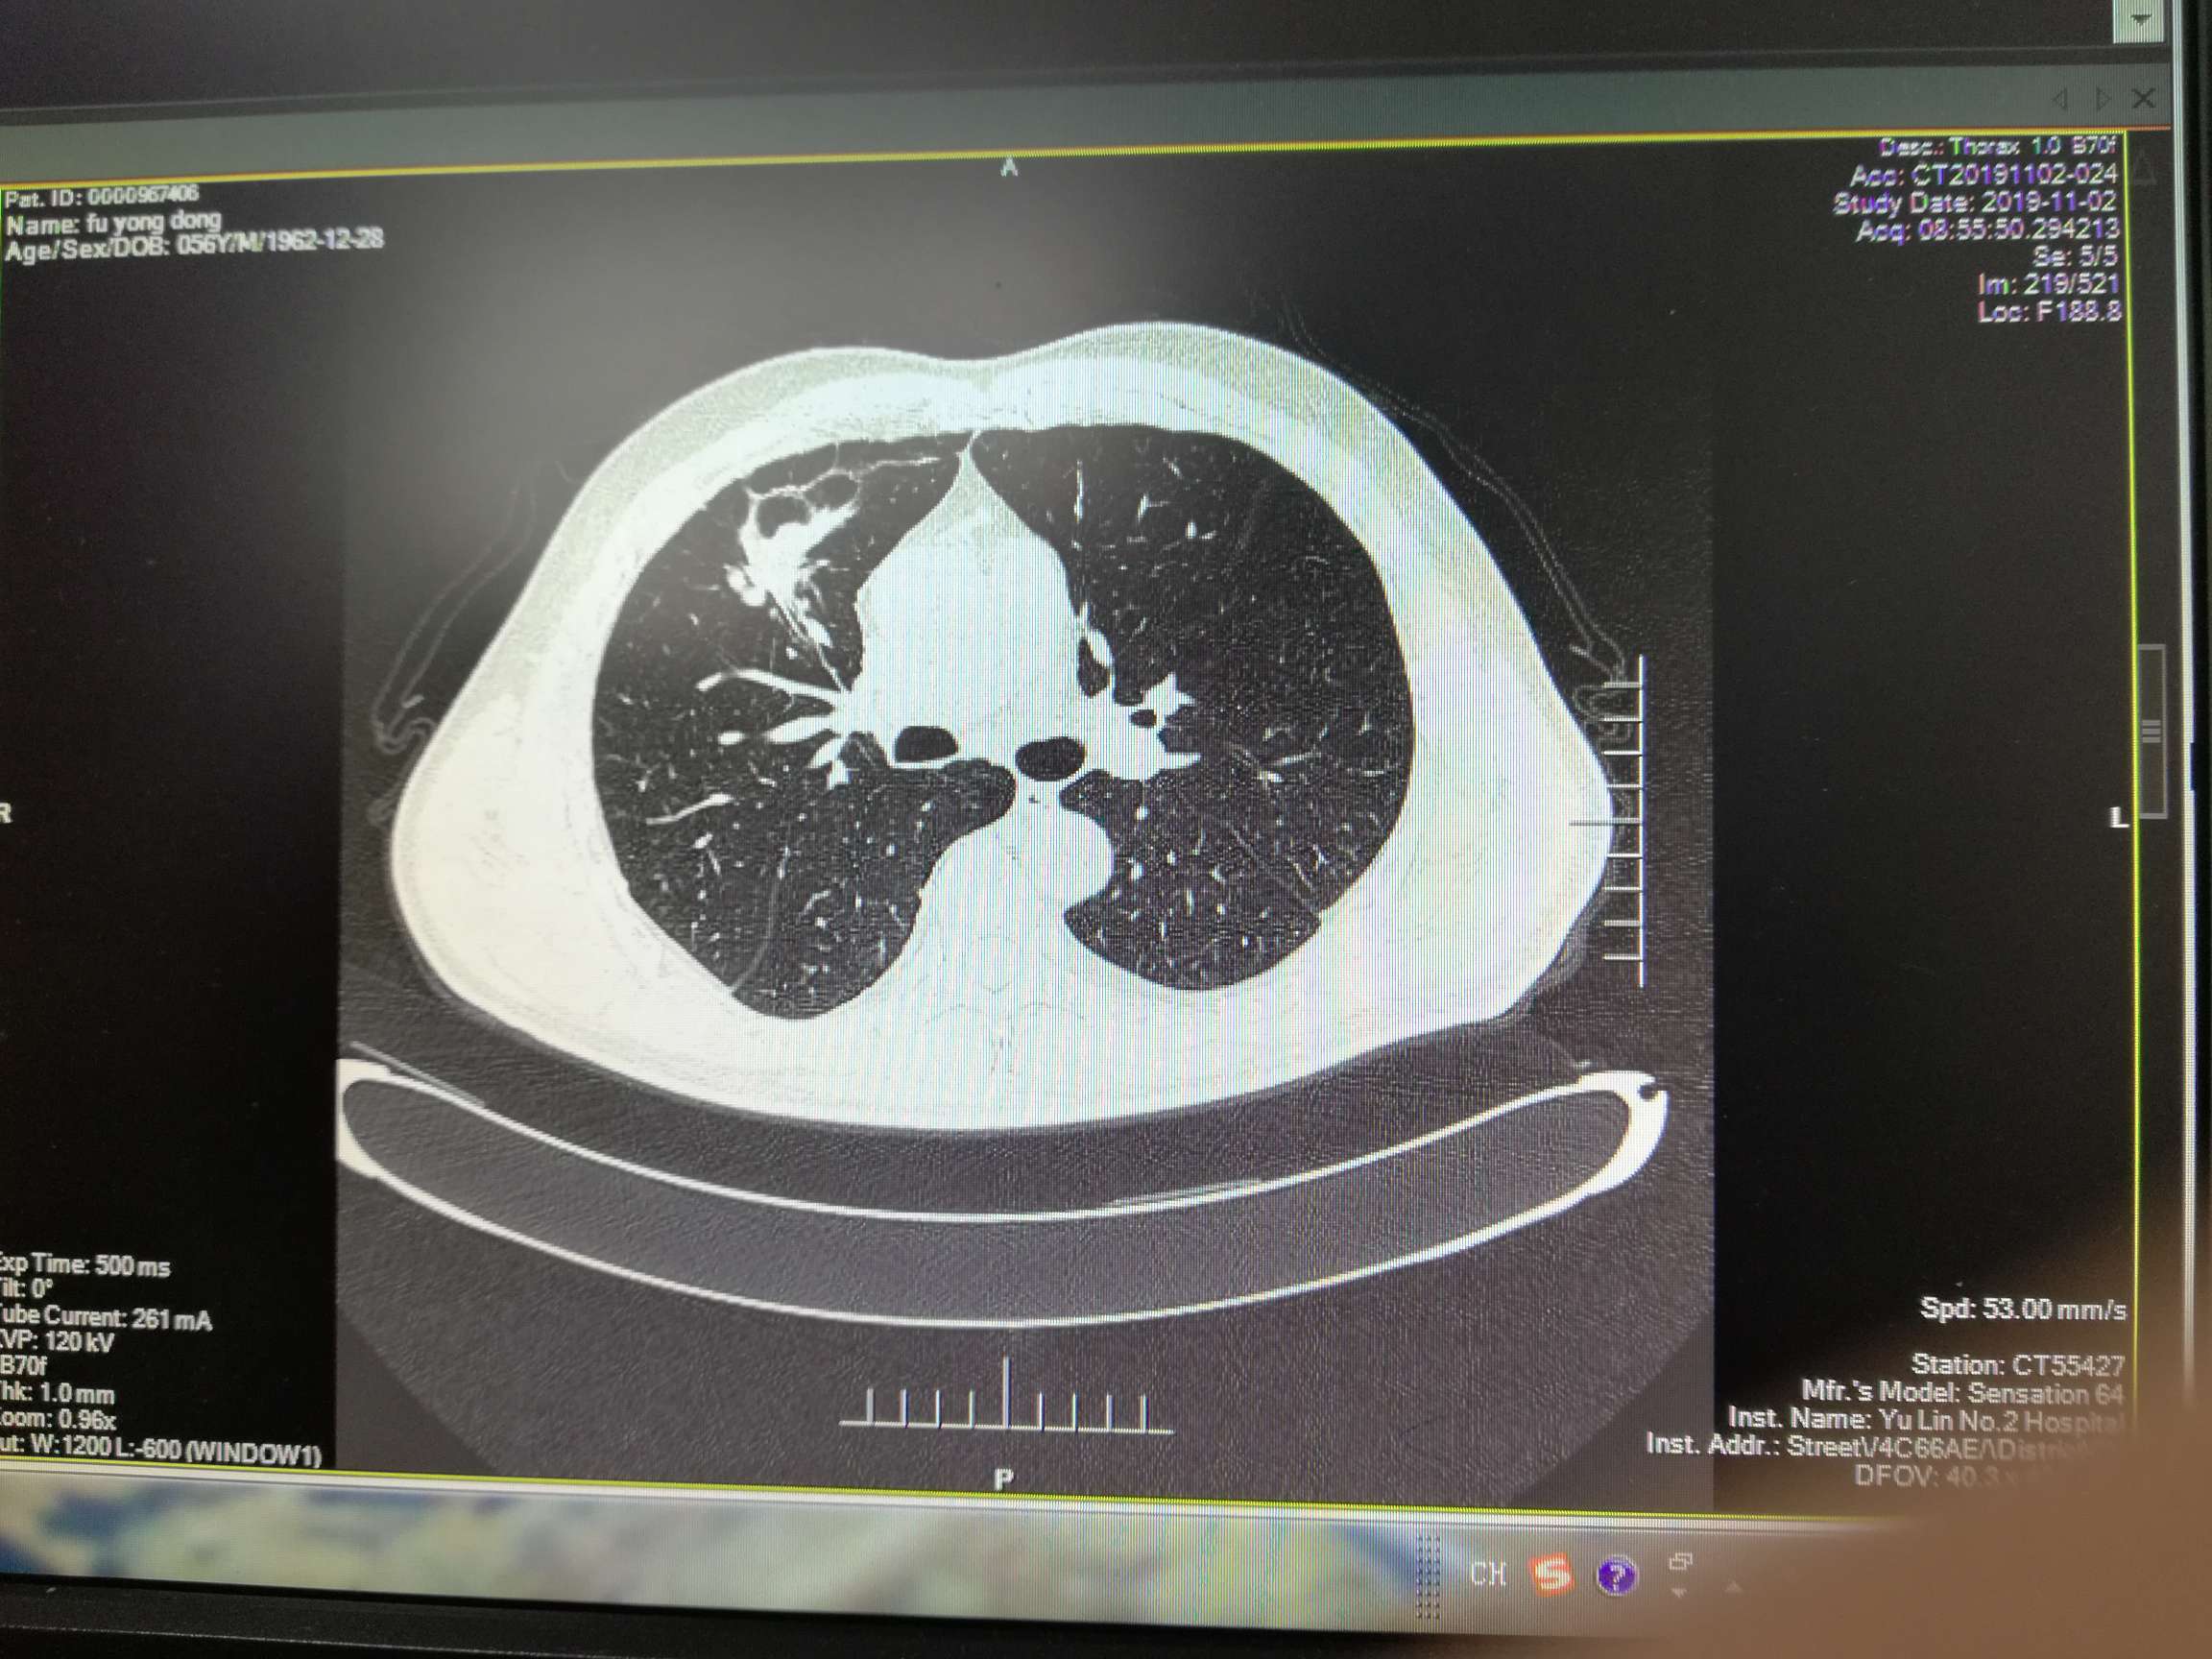

胸部右肺叶前段有3.4*6.7cm原发灶,右侧叶间裂、胸膜多处转移,纵膈内、右肺门旁、心隔角多处淋巴结转移,较大者1.3*1.0cm。有少量胸水。

期间病情迅速控制,原发灶从6. 7*3.4cm减小为1.7*1.5cm,头部从2.4*1.8cm减小到1.1*0.9cm,淋巴结较大者一直为1.3*1.0cm。胸水抽了两次,打了恩度,之后胸水没有再犯。肿瘤指标物一直减小。骨髓抑制严重。

10月份复查,cea继续缓慢上升,糖类125也开始上升。Ct显示原发灶从1.4*1.2cm增大到为2.7*1.4cm。pet-ct显示没有远端转移,头部转移灶失去活性,胸部原发SUVmax4.2,淋巴结SUVmax3.2。骨髓抑制现象继续持续,白细胞3.8,淋巴细胞百分比46.3%,中性细胞36.10%。在用K药之后再测白细胞3.2,可能骨髓抑制与K药有关。病人体感很好。总体判断为耐药迹象。